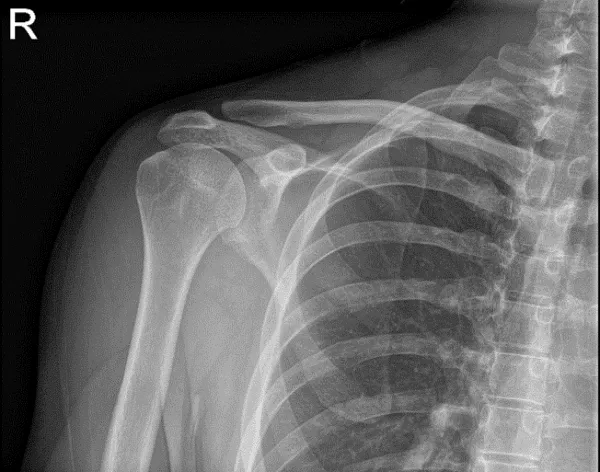

Bilateral Shoulder X-ray AP External and AP Internal